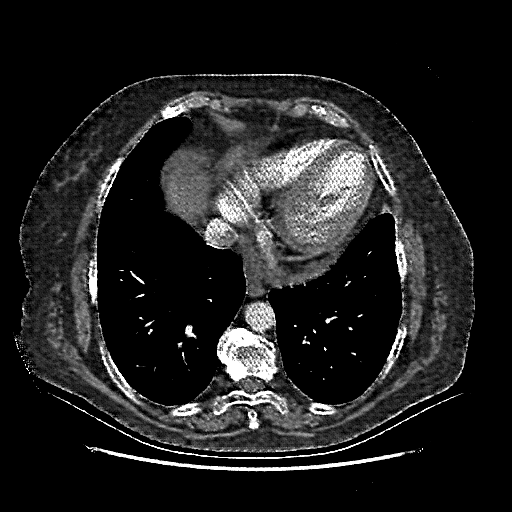

Original VENOUS CT scan

No window - Raw intensity values